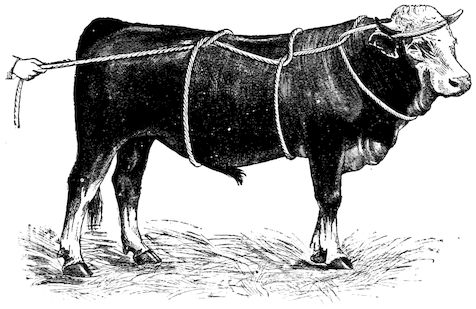

3. The third phase is characterised by fractures, and it is this peculiarity of the disease which has procured for it the names of fragilitas ossium, and osteoclastia. These fractures may affect any portion of the skeleton. Animals so suffering sometimes break a leg whilst trotting or the pelvis in simply jumping over a ditch; a collision with a fixed object like the jamb of the stable door, or a fall on the ground, may result in the fracture of one or several ribs.

Fig. 3.—Pig suffering from osseous cachexia (fourth stage).

Such shocks would be of no importance to a healthy animal, but to one suffering from osseous cachexia, any violence, or even the slightest muscular effort may be followed by fracture of the gravest character, involving even the vertebral column. In cows the pelvis, femur, and tibia are most frequently injured.

In horses, particularly in riding horses, fractures are commonest in the region of the forearm, cannon bone, and anterior phalanges. So extremely fragile are the bones at this stage that the horse represented herewith broke twelve ribs at one time by simply falling on its side. It is interesting to note that such fractures are never accompanied by any extensive bleeding. They have little tendency to repair, no real callus formation occurs, and on post-mortem examination one often finds the ends unconnected by temporary callus, worn, and rounded by reciprocal friction.

At this stage but under other circumstances, the animals show great reluctance to rise, remaining down for twelve to twenty-four hours without shifting their position. If forced to get up, they stand as though fixed in one position, the respiration and circulation become rapid, and they soon grow tired and fall.

114. The fourth phase, or period of osteomalacia, i.e. softening of the bones, is also the last. It is rarely seen in large animals like horses and oxen, because accidents so often accompany the preceding stages and necessitate slaughter; but it is common in goats and pigs.

In this phase the bones become elastic, soft and depressible, yielding to the pressure of the operator’s fingers.

Fig. 4.—Deformity of the face in the horse shown in Fig. 2.

The flat bones are particularly liable to this change, which is common to domesticated animals. The bones of the head are the first to suffer; later those of the pelvis. The lower jaw becomes swollen, particularly about the centre of the branches which may attain three, four, or five times, their normal thickness.

The depression in the submaxillary space disappears. The upper jaw undergoes similar changes, becoming deformed and thickened until the cavities of the sinuses and the hollow appearance of the palate are lost, while the face is so changed that it cannot be recognised as that of a horse, goat, etc.

The molar teeth are almost buried, their tables alone being visible at the bottom of a depression, the edges of which rise above the neighbouring parts (pig).

Mastication is clearly impossible, the jaws appear paralysed, the muscles powerless, and only swallowing is possible, a fact which explains why life is only prolonged to this stage in animals which can be fed with a spoon or bottle (pigs and goats). The bones of the cranium, although greatly changed in texture, are always less deformed than those of the face.

The changes are such that it is often easy with a mere post-mortem knife to cut the head completely in two. Osseous tissue, properly so-called, has disappeared.

All the constituent tissues, with the exception of the skin and muscles, i.e., the bone, periosteum and aponeuroses, have the appearance and consistence on section of the fibro-lardaceous tissue seen in chronic inflammation.